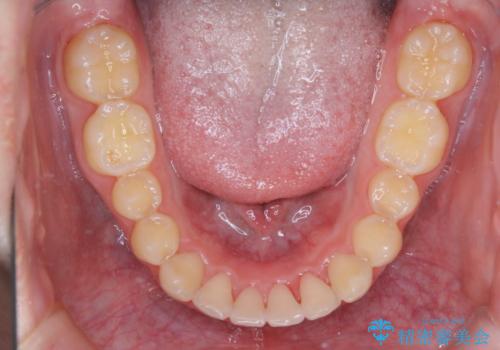

- 上の前歯が見えすぎて気になるとご相談にいらした方です。インビザラインにて前歯の圧下を行うことで歯の見え方の改善し、同時に奥歯の噛み合わせも改善を行いました。

インビザラインを正しく使用して頂けたおかげで、比較的難しいとされる歯の圧下も補助装置を使用せずに行うことが出来ました。上の前歯のラインが整ったことで笑った時の口元の印象を改善させることができ、大変喜んでいただけました。